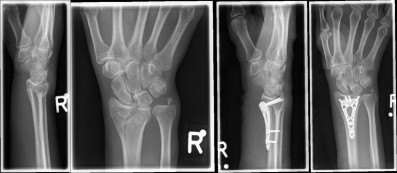

Handgelenk 3

Pictures: A distal radius fracture with joint involvement (C-fracture) was treated with a plate osteosynthesis. After surgery, the plaster can be removed and physiotherapy exercises can be performed.

Complicated fractures involving the articular surface or dislocation should be surgically treated. Open fractures in which the skin is injured and bone is exposed require immediate surgical care. An involvement of the articular surface can lead to a restriction of the mobility in the wrist and therefore requires an anatomically exact reduction. The standard procedure for distal radius fractures is the provision of a titanium plate applied by the diffraction-side (palmar plate osteosynthesis) or the application of an external holder (external fixator).